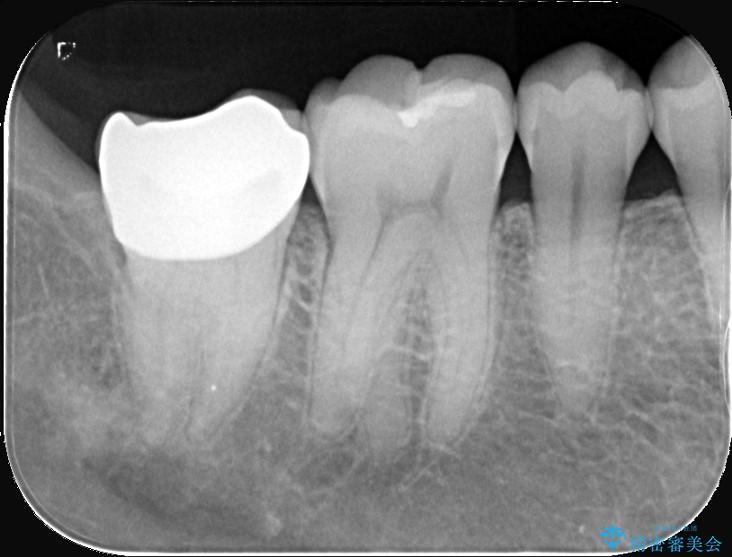

歯と歯の間に虫歯があった患者様です。

噛む面や外側にも過去の詰め物が入っている状態で、このように詰め物の範囲が大きいと治療後に歯が割れてしまうリスクが高くなります。

今回は歯の強度と将来的な破折リスクを考慮し、セラミッククラウンによる治療を行うこととしました。